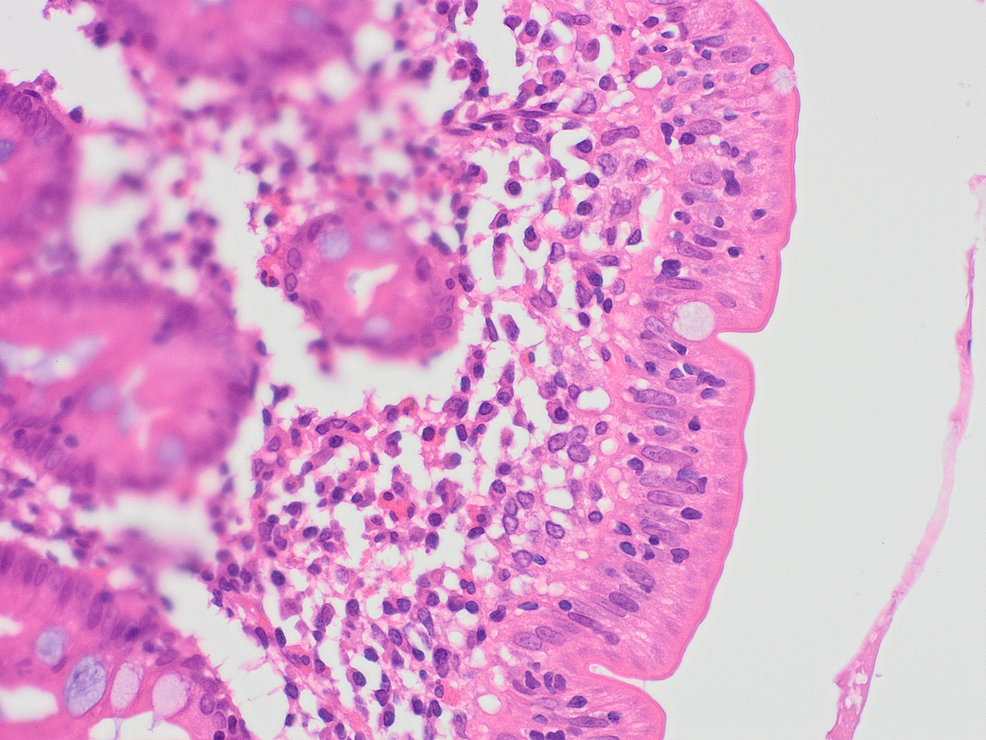

Following the results of the abdominal and pelvic CT, an exploratory laparotomy was performed and a wedge biopsy of the ileal and right colonic wall was sent for histopathological analysis. Pathology subsequently revealed a florid acute serositis with the marked expansion of the subserosal fatty tissue with a hypereosinophilic cell population identified in the right colonic and terminal ileum mucosa and lamina propria (Figures 2-5). There was no evidence of any microorganism, vasculitis, or malignancy including lymphoma.

Given the presence of a significant eosinophilic cell population in a non-neoplastic setting, pathology recommended investigating two distinct differentials: hypersensitivity eosinophilic type inflammatory process and a parasitic infection given the patient’s travel and occupational history. Immunology and infectious disease were thereby consulted.